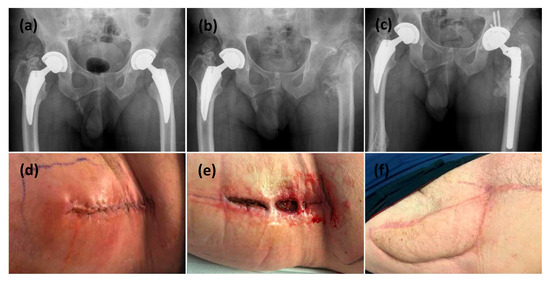

All patients had retained implants at final follow-up, either through initial implant retention or successful reimplantation (Table 3). Two patients had their implants removed prior to VRAM flap reconstruction as part of infection control (Figure 1). Following reconstruction, both achieved successful infection eradication and proceeded to prosthesis reimplantation. The remaining three patients retained their implants at the time of VRAM flap reconstruction and underwent extensive debridement with modular component exchange (Figure 2). Of these, one achieved complete wound healing and infection control. The other two experienced persistent infection—one required flap elevation, five additional debridements, and a two-stage revision. Despite the prolonged course, infection was ultimately eradicated, and reimplantation was performed 2 years and 8 months later, with the flap remaining viable throughout. The second patient continued to have a draining sinus but retained the implant. A summary of procedures and outcomes is shown in Figure 3.

Figure 2. This is a figure of left hip PJI with all revisions performed through a posterior surgical approach. (a,d) radiographic and clinical presentation with initial symptoms of PJI, (b) The patient underwent a stage-1 revision with an antibiotic-cement spacer, (e) wound dehiscence at 4 weeks post spacer implantation, (c,f) The spacer was then revised to Stage-2 definitive implant with a VRAM flap at the same time.